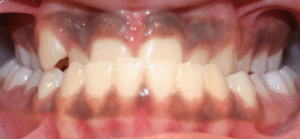

Open Bite

An open bite occurs when there is insufficient vertical overlap of the teeth. It is caused by oral habits such as a tongue thrust, thumb or finger sucking or when the jaws don’t grow evenly. Timing of treatment is critical to the overall success of the therapy.

How can an open bite be orthodontically corrected?

An open bite can be corrected through growth modification of the jaws using braces, extrusion of the anterior teeth and in some cases surgical correction of the jaws. Also breaking oral habits, such as digit sucking, will facilitate the correction of an open bite.

Before and After Photos: Open Bite Correction